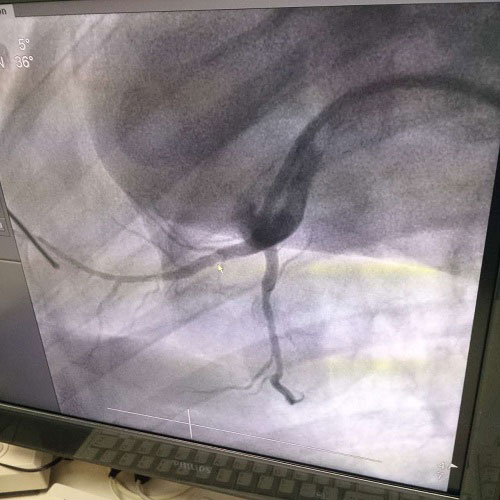

生物全降解鎂合金藥物洗脫支架是我由公司自主立項研發(fā)、主要工藝技術(shù)完全自主,具有完全自主知識產(chǎn)權(quán)。并且可行性強,前期研發(fā)基礎(chǔ)扎實,市場需求迫切,實施風(fēng)險可控,屬全球同行業(yè)領(lǐng)先技術(shù),填補國內(nèi)技術(shù)發(fā)展空白,符合國家產(chǎn)業(yè)發(fā)展政策,社會、經(jīng)濟效益巨大。目前鎂合金藥物支架已進(jìn)入動物實驗階段,植入動物體內(nèi)一個月之后效果良好。